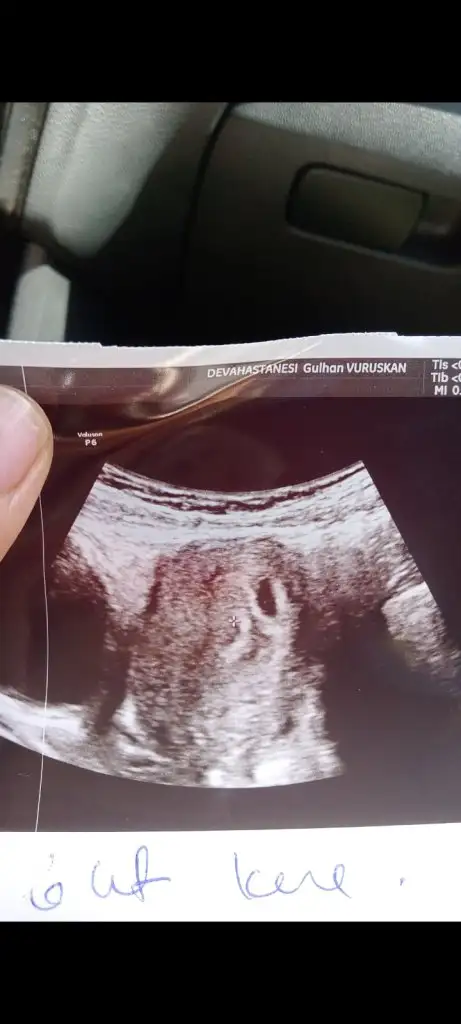

Karından hepsi banada bakabilir misiniz

Canım ya banada bak meraktan öleceğim ilk atacağım foto 6 haftalık sonraki 9 ikiside karından